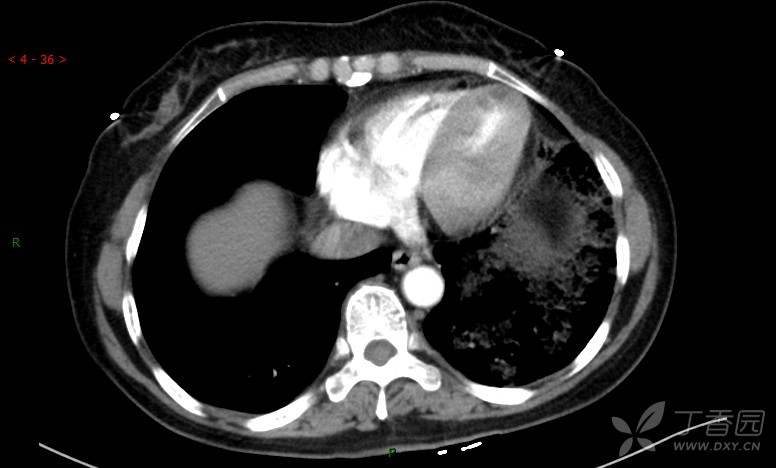

腺泡结节影,蜂窝征,这些都在提示……(病例3连发,附其他2例链接,病理已公布)

原帖名:胸部典型病例3(病例3连发,附其他2例链接)

咳嗽1年余,加重7天。

患者于1年余前始受凉后出现咳嗽,多为干咳,未在意,未到医院就诊。近3月患者出现咳痰,多为黄色粘痰,量大,伴乏力,偶有头晕、心慌,无发热、胸痛、憋喘,无低热、盗汗、咯血、胸痛,无头痛,无恶心、呕吐、腹痛、腹泻,无尿频、尿急、尿痛,在当地诊所给予抗感染等对症支持治疗(具体药物及剂量不详),症状仍时有反复。患者于1月余前到外院就诊,行胸部CT提示双肺炎症,左肺重,考虑为“间质性肺炎”,给予“左氧氟沙星、利巴韦林、头孢哌酮舒巴坦钠注射液”治疗,复查胸部CT示病灶吸收不理想,后出院继续于诊所对症治疗(具体药物及剂量不详),效果欠佳。7天前患者无明显诱因出现上述症状加重,为求进一步诊治,特来我院就诊,我院门诊以“肺炎(重症)?”收入留观室,留观室给予“盐酸莫西沙星氯化钠”等对症治疗后,今日转入我科。患者自发病以来,神志清,精神差,饮食正常,睡眠增多,大小便正常,体重近3月减轻5公斤余。